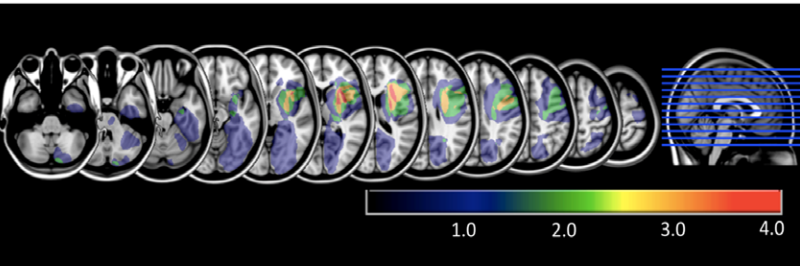

Our research integrates MEG and EEG with neuroimaging ( 1 , 3), including MRI and lesion-based analyses, to understand how neural signals are constrained by underlying neuroanatomy. Méadhbh’s Nature Human Behaviour study combined EEG with MRI and linked individual differences in neural markers of sensory evidence accumulation with structural and functional connectivity in dorsal fronto-parietal regions.

3. Brosnan et al. (2020). Nat. Hum. Behav.

Our data combined diffusion MRI, resting MRI, and EEG to reveal a specific structural and functional network underpinning differences in the rate of sensory evidence accumulation and the timing of perceptual decision.